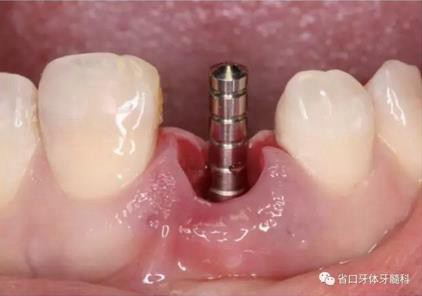

(1)微創(chuàng)拔牙及即刻種植:術(shù)前拍攝口內(nèi)照及實(shí)施牙周基礎(chǔ)治療。常 規(guī)消毒鋪巾阿替卡因局麻下微創(chuàng)拔除上頜右側(cè)中切牙,搔刮拔牙窩及根尖肉 芽組織。探測牙槽骨唇側(cè)骨壁及鄰面牙槽嵴完整,牙齦無撕裂。不翻瓣下于上頜右側(cè)中切牙缺隙近遠(yuǎn)中中點(diǎn)的腭側(cè)牙槽骨及根方定位,按照逐級預(yù)備的原則,緊貼牙槽窩腭側(cè)骨壁制備種植窩洞,植入Zimer®3.7mm×13mm TSV種植體1顆,植入扭矩>35N·cm,以O(shè)sstell測量種植體的ISQ值為68。 種植體平臺(tái)位于唇側(cè)齦緣中點(diǎn)下3mm,與唇側(cè)骨壁內(nèi)側(cè)面形成的跳躍間 隙約2mm,置入Bio-Oss®細(xì)顆粒骨粉0.25g,上愈合基臺(tái)關(guān)閉創(chuàng)口。術(shù)后 CBCT檢查顯示:種植體利用牙槽窩根方骨質(zhì)固位,緊貼牙槽窩腭側(cè)骨壁, 其唇側(cè)面與牙槽窩唇側(cè)骨壁的內(nèi)側(cè)面所形成的跳躍間隙(約2mm)可見顆 粒狀顯影物充填。牙槽窩的唇側(cè)骨壁及唇側(cè)倒凹無缺損穿孔。

圖15 植入種植體并置入覆蓋螺絲

圖16 跳躍間隙植骨

圖17 跳躍間隙植骨

圖18 測量ISQ值